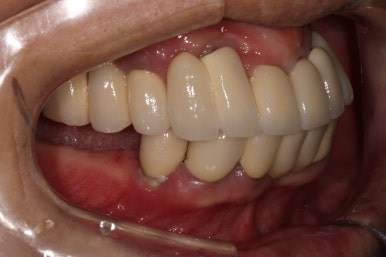

차이를 별로 못느끼실 수 있겠지만, 임플란트 보철물 완성 6개월 후 방문 때 구강내 사진입니다.

감사히도 환자분께서 상당히 깨끗하게 유지하고 계셔서, 잇몸에 염증하나 없이 너~무 보기 좋더라구요.

임플란트도 6개월에 한 번씩 스케일링을 받으셔야 합니다.

치아랑 똑같이 치태도 쌓이고 치석도 생긴답니다.

결국은 자연치아의 만성치주염에 해당하는 임플란트주위염으로 발전할 수 있기 떄문에, 자가 관리를 확실히 그리고 철저하게 하시는 것이 매우 중요해요!!!

그래도 대부분의 환자분들은 고생해서 받은 임플란트 치료 결과를 잘 유지하기 위해 치간칫솔, 칫솔, 워터픽 등 수단을 가리지 않고 열심히 관리해주시더라구요!